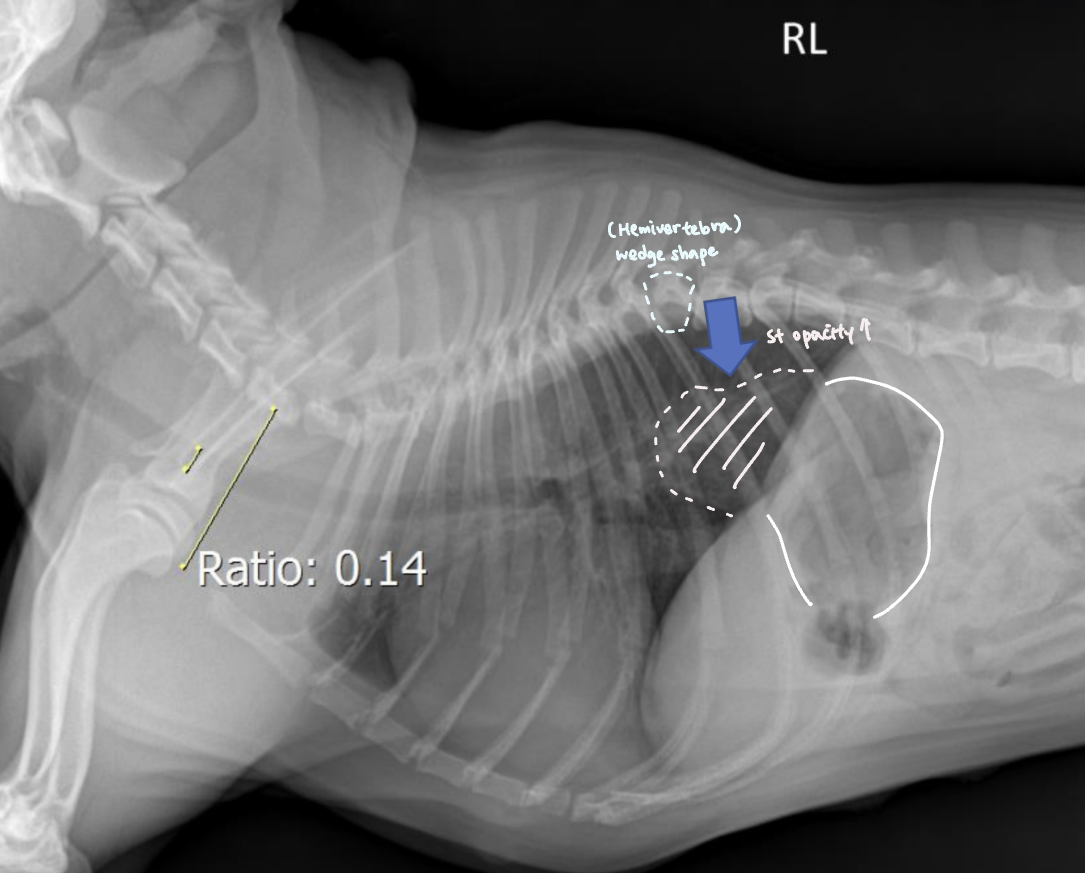

Tracheal diameter ์ฌ๋ ๋ฒ๋ฒ

- Thoracic inlet๊ณผ์ ๋น์จ๋ก ๋ํ๋ธ๋ค.

![]() | - T1์ ๋๋ถ๋ถ์์, 1๋ฒ sternum์ ๊ฐ์ฅ ์ค๋ชฉํ ๋ถ๋ถ (Thoracic inlet)์ ์ ์ผ๋ก ์๊ณ ๊ธธ์ด๋ฅผ ์ฐ๋ค. - Trachea์ ๊ธธ์ด๋ฅผ ์ฐ๋ค. - ๋น์จ์ ๋ณดํต 0.2 ์ ๋. ![]() (๋จ๋์ข ์์๋ ์ ์์ ์ผ๋ก ๋ ์๋ค.) |

Tracheal hypoplasia

| Tracheal hypoplasia |

|---|

| ๊ธฐ๊ด ์ง๊ฒฝ์ ๊ฐ์, ๋จ๋์ข

์์ ํํจ - Bulldog์ ์๋ ์์์ 9% ์ดํ๋ถํฐ ์ด์ ์๊ฒฌ - ๊ธฐ๊ด์งํ๋ ด(Bronchopneumonia) ๋ค๋ฐ - ๋ค๋ฅธ ์ ์ฒ์ ์ด์, ์ฌ๋ฐ๋ ํํจ - ๊ธฐ๊ด์ด ๋ง๋ ค๋ค์ด๊ฐ๋ฉด์ ์ข์์ง๊ธฐ ๋๋ฌธ์ cilia ๊ธฐ๋ฅ X, ๊ธฐ๋ฅ์ ์ผ๋ก๋ ๋ง์ด ๋จ์ด์ง |

![]() |